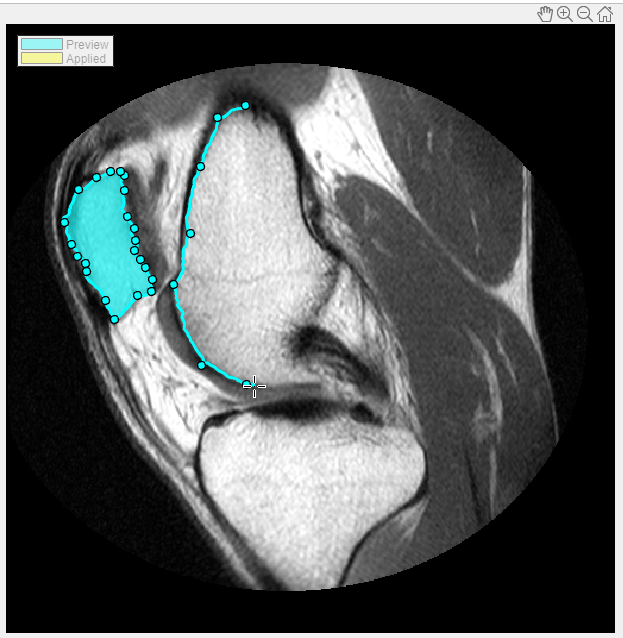

Seleccione el tipo de ROI que desea dibujar. Para este ejemplo, elija Assisted Freehand. Al mover el cursor por la imagen, cambia a la forma de retículo. Pulse el botón del ratón y empiece a dibujar una forma a mano alzada sobre la parte de la imagen que desea segmentar. Con la opción de ROI Assisted Freehand, que está preseleccionada, puede dibujar una forma a mano alzada que sigue automáticamente los bordes de la imagen subyacente para ayudarle a dibujar una ROI más precisa. Mientras dibuja, haga clic con el ratón para crear waypoints. Los waypoints pueden ayudarle a realizar ajustes precisos en la forma después de terminar de dibujar. Para agregar waypoints adicionales después de terminar de dibujar, haga doble clic en el borde de la ROI.

Continúe dibujando formas hasta identificar todas las áreas que desea segmentar. Para guardar las regiones que ha dibujado, haga clic en Apply (su color cambia a amarillo). Para volver a la pestaña Segmentation, haga clic en Close ROI.